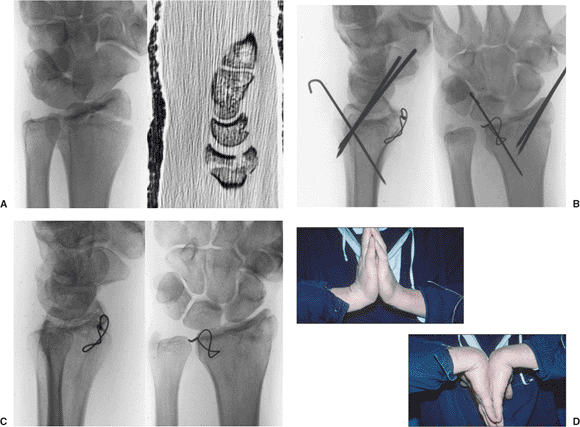

Figure 13.14.

Fixation of a displaced, rotated, volar, ulnar, lunate-facet fragment can be done using a small gauge wire looped through the volar capsule and radius in a figure-of-eight fashion. A. Preoperative x-ray and CT scan reveal a displaced, volar, lunate facet. B. The radial styloid and dorsal lunate facet could be reduced and held with K wires, but the volar lunate facet required open reduction and wire loop fixation. C. Healed fracture at 1 year. D. Clinical wrist motion. |